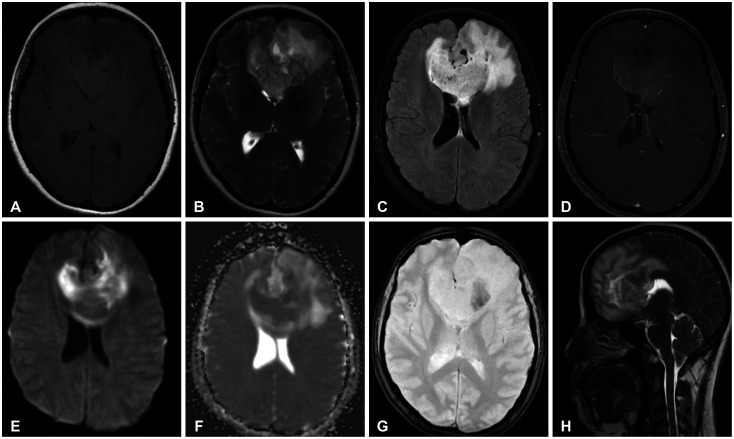

We discuss a patient with a tumor on the anterior corpus callosum who underwent open biopsy eventually succumbing to cerebrogenic fatal arrhythmia following wounded glioma syndrome. A healthy 37-year-old female patient was admitted to our department due to a history of headache for 13 months. MRI revealed a suspicious glioma infiltrating the anterior corpus callosum. Neurologic examination only showed low cognitive assessment score (Montreal Cognitive Assessment score 20/30). ECG was normal sinus rhythm. Steroids and levetiracetam were administered prior to operation. Patient underwent right frontal craniotomy and biopsy of tumor with unremarkable events. During the first hospital day, patient had episodes of bradycardia followed by decrease in sensorium. Brain CT scan showed progression of edema without hemorrhage within the tumor bed. This was followed minutes later by two episodes of generalized tonic-clonic seizures and pulseless ventricular tachycardia. Cardiac resuscitation was done for 24 minutes but patient eventually expired. Location of the lesion and the epileptogenicity of the peritumoral cortex greatly contributed to the patient's demise. Involvement of the fronto-mesial structures, particularly the insula and the cingulate cortex, and their connection to the central autonomic network, increased susceptibility to arrhythmias. Decreased seizure threshold worsened post-operative edema, further aggravating the dysregulation of the brain-heart-connection.